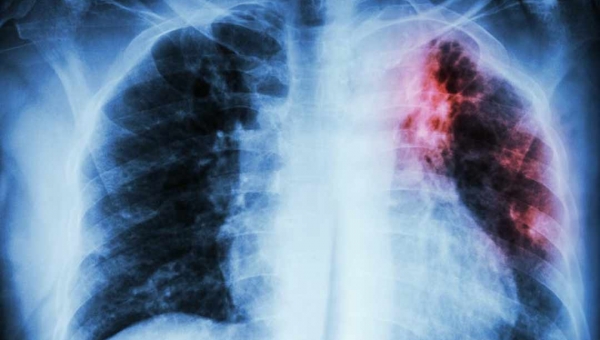

Covid-19: Acre registra mais 193 casos e duas mortes em um dia